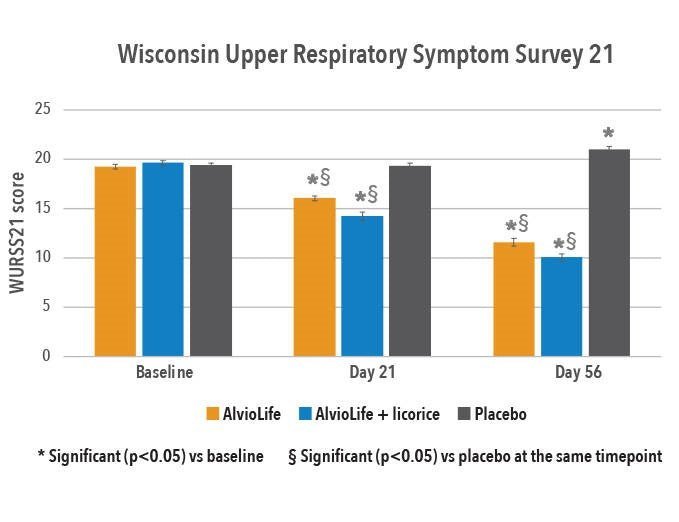

Etude clinique sur AlvioLife® pour le confort respiratoire – Revue internationale des sciences médicales (2021)